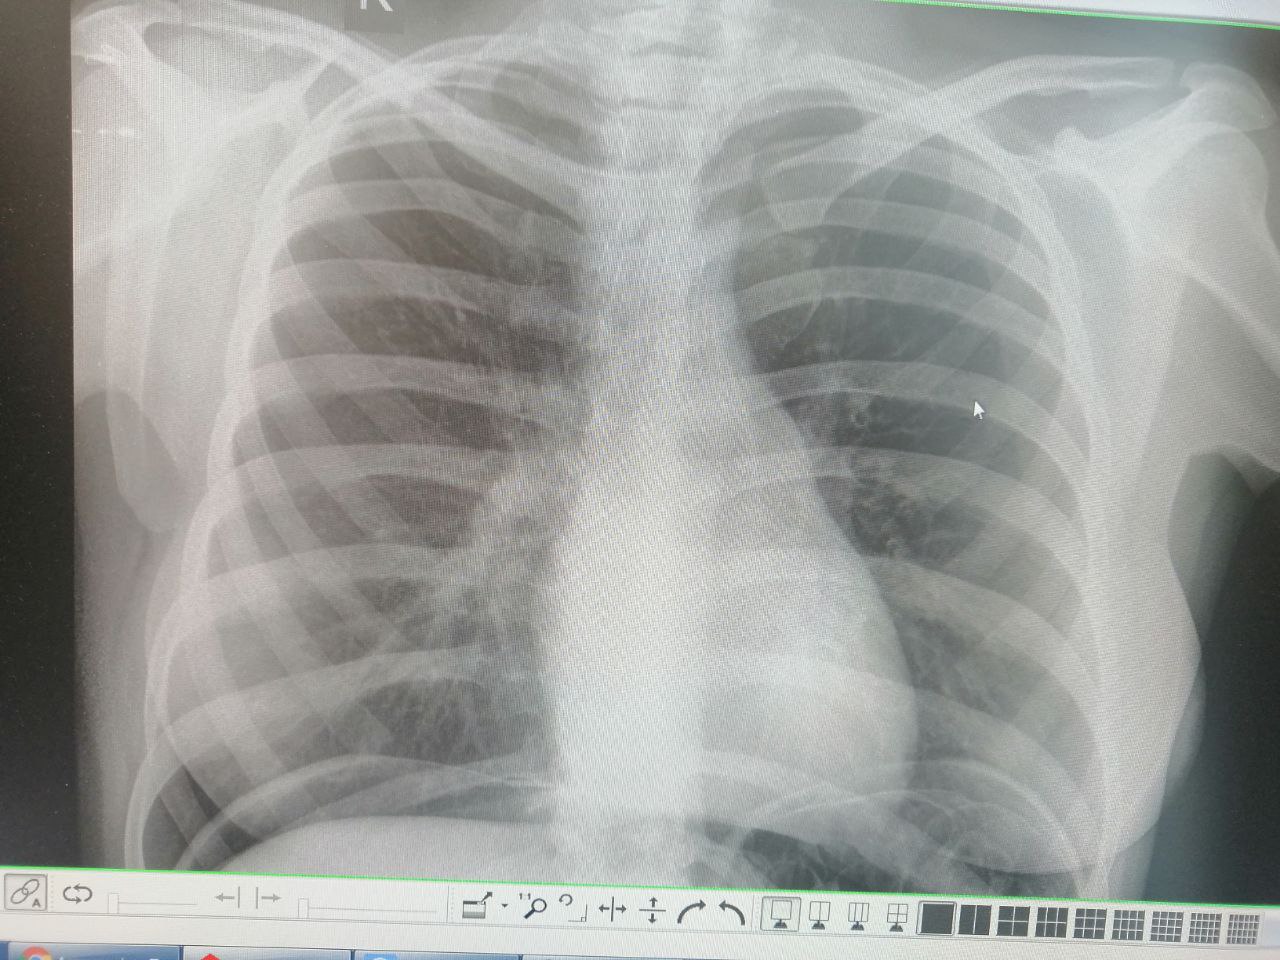

Здравствуйте. Девушка 1999г.р. Про. Осмотр. Что то слева может быть?

пневмоторакс?

Пневмоперитонеум помлеоперационный вижу. А пневмоторакса нет. Я спрашиваю за эту штуку

Левый боковой сделайте

Отправьте на кт

А что это может быть?